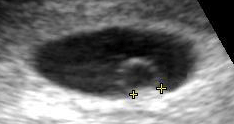

Contents in the cavity of the uterus seen at approximately 5 weeks of gestational age by obstetric ultrasonography.

Artificially colored, showing gestational sac, yolk sac and embryo (measuring 3 mm as the distance between the + signs).